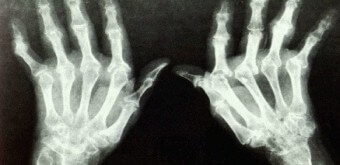

류마티스 관절염은 관절을 감싸고 있는 활막에 만성적인 염증이 발생하는 질환으로 자가면역 반응으로 인해 시작되며, 시간이 지나면서 관절 연골과 뼈에 손상을 일으킬 수 있습니다. 특히 손가락, 손목, 무릎 등 비교적 작은 관절에서 양쪽에 대칭적으로 발생하는 경우가 많습니다.

활막의 염증이 계속되면 관절 내부 공간이 좁아지고, 점차 관절 변형이나 운동 제한으로 이어질 수 있습니다. 단순히 관절에만 국한되지 않고, 혈관, 폐, 눈 등 전신에 영향을 미치는 경우도 있습니다. 비교적 천천히 진행되지만, 초기부터 적절한 관리가 이루어지지 않으면 구조적 손상이 누적되기 쉬운 특징을 가지고 있습니다.

관절 변형은 관절염의 진행에 따라 관절의 모양과 구조가 변경되는 것을 말합니다. 특히 손가락 관절에서 두드러지며 손가락이 이상한 방향으로 구부러지거나 마비되는 현상을 볼 수 있습니다. 이러한 변형은 연골이 파괴되고 주변 조직이 변화하는 과정에서 발생합니다.

손가락을 움직이면 관절이 비정상적인 각도로 굽히거나 움직임이 제한되는 문제가 생깁니다. 이로 인해 물건을 잡는 것이나 작은 움직임도 어려워집니다. 일상생활에서 손을 활용하는 다양한 작업, 예를 들어 글쓰기, 물건을 들거나 이동시키기, 세밀한 작업 등에 어려움을 줄 수 있습니다.